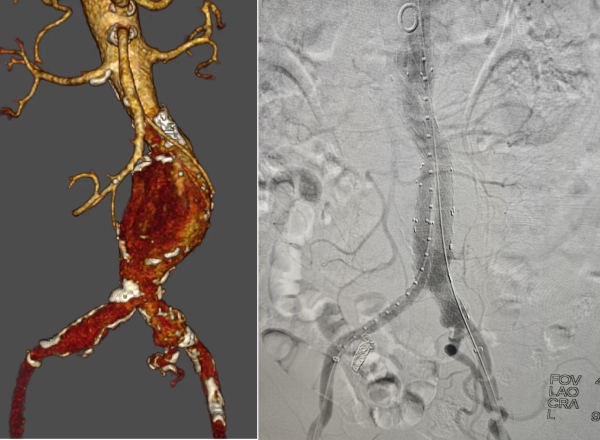

患者1术前、术后影像

患者1张某,男性,68岁,以“发现腹部包块1周余”主诉入院,腹部包块伴有压痛,患者既往有冠心病史,并多次行支架植入以及药物治疗。患者2李某,男性,73岁,患者既往有高血压病史10年,口服药物控制,7年前出现脑梗,患者辗转多家医院未予以明确诊断,慕名来我院求医。以上两位患者基础病复杂,身体条件较差,马建仓主任带领医护团队利用扎实的专业知识,迅速做出明确诊断,医护紧密协作,各司其职,细致入微的诊疗氛围,在治疗身体疾病的同时,为患者纾解心理压力,让整个围术期都在安全、信任、放心的过程中展开。

腹主动脉瘤是血管外科疾病中非常凶险的一类血管病变,对医生的操作技术有着非常严苛的高要求和高标准,通过腔内介入技术,进行腹主动脉瘤的腔内隔绝,术中克服血管多发钙化、扭曲,经过精确的计算、精准操作,保护肾动脉、髂内动脉等关键血管,覆膜支架不能有毫厘之差,完全覆盖病变段血管,主体植入后根据病情需要,还要左右侧腿的拼接,狭小的操作空间,需要严丝合缝的对接,对医生的技术也是一项高难度的考验,2例患者平均手术时间为120分钟左右,平均住院日均为4天,术后患者恢复良好,已顺利出院。血管外科团队在马建仓主任的带领下,短短不到两个月的时间,克服人员紧缺、工作量大的各种困难,在平均住院日、床位使用率、各项手术指标,以及经济指标方面都取得一路向上的良好成绩。在专业的学科道路上越走越稳,越走越远。